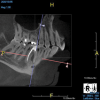

(11.) A pathosis apical to the maxillary central incisors was initially not diagnosed after evaluating the periapical film; however, the CBCT image revealed its presence. Only using the CBCT image could it be determined that the lesion was not odontogenic in origin and that it did not involve the nasopalatine foramen. This diagnosis was supported by a referral to an oral and maxillofacial radiologist.

Figure 11

(12.) A pathosis apical to the maxillary central incisors was initially not diagnosed after evaluating the periapical film; however, the CBCT image revealed its presence. Only using the CBCT image could it be determined that the lesion was not odontogenic in origin and that it did not involve the nasopalatine foramen. This diagnosis was supported by a referral to an oral and maxillofacial radiologist.

Figure 12